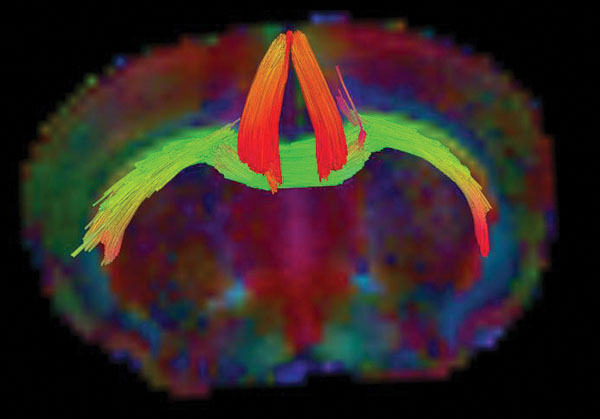

An MRI tractography image of a mouse brain that has both ADHD and concussion. The colors denote different directions in which water is moving through bundles of neurons.

But even with a well-suited model, stripping back the convoluted layers of these interactions is no easy feat. Clinical-grade magnetic resonance imaging (MRI) technologies, which doctors use to snap detailed pictures of the brain, aren't strong enough to produce the kind of highresolution images needed to credibly explore these infinitesimal effects. A complicated mystery requires more powerful tools.